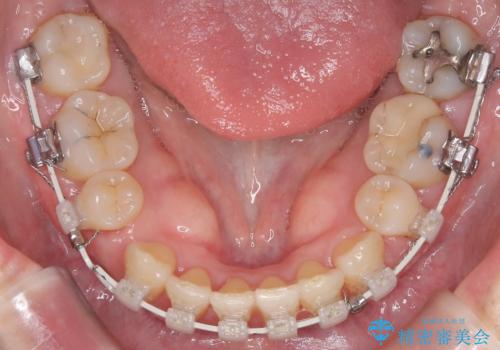

- 前歯の凸凹と前突感を改善するため、上下左右の4番を抜歯し、空いたスペースを利用して前歯を後方へ下げる審美ワイヤー矯正を計画しました。抜歯後は透明で目立ちにくい審美ブラケットを装着し、ワイヤーを用いて徐々に歯列を整えます。毎月1回の調整を通じて歯並びの変化を確認しながら、丁寧に矯正を進め、約2年で理想的な歯列と噛み合わせを完成させることを目指します。

前歯が前に出ていることや歯並びの凸凹が気になるという主訴でした。十分なスペースを確保するため上下左右の第一小臼歯(4番)を抜歯し、そこに前歯を移動させて整列を行いました。矯正装置には目立ちにくい透明なブラケットを選択し、見た目のストレスを軽減。矯正期間中は定期的な通院でワイヤーを微調整し、無理なく確実に歯を動かしました。治療後は前歯が自然な位置に下がり、口元の突出感が解消されるとともに、美しく整った口元に仕上がり、患者様にも大変喜んでいただけました。